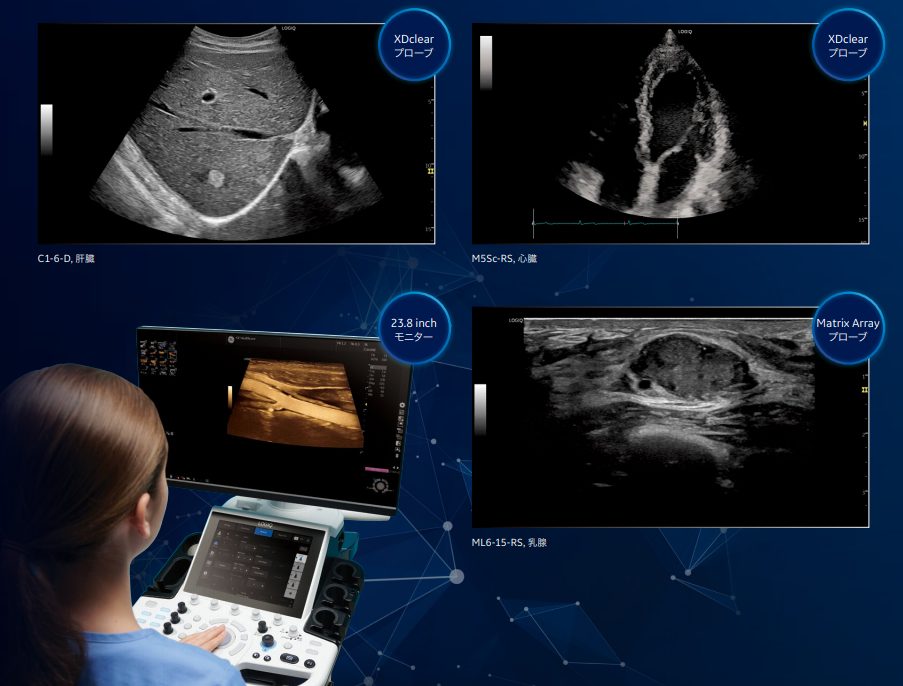

Shear Wave Elastography

シングルモードとマルチモードによる簡便な操作性を実現。

Quality Mapに基づいて精度の高い領域で計測でき、

様々な臓器に対し、組織の硬度を計測可能です。